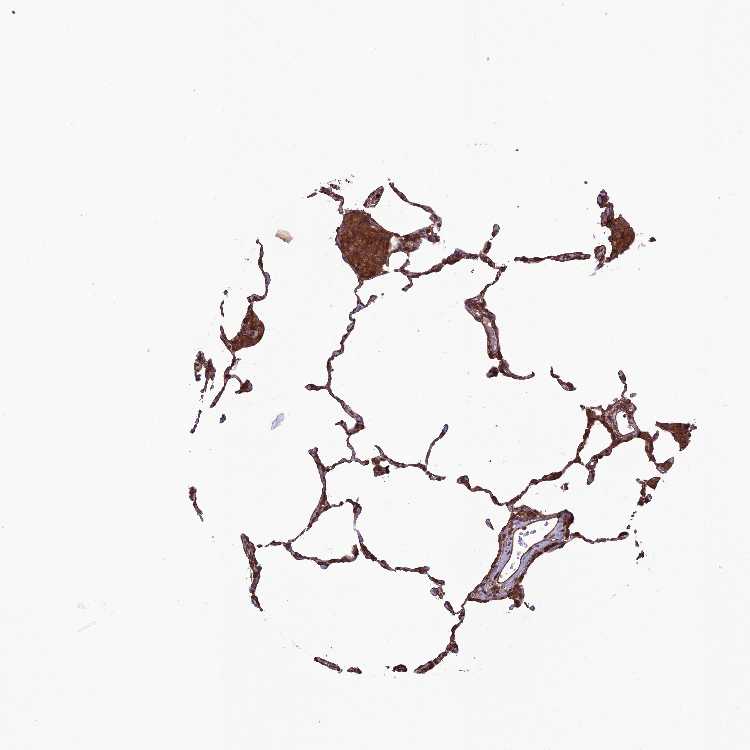

Antibody staining in the annotated cell types in the current human tissue is reported as not detected, low, medium, or high. This score is based on the staining intensity and fraction of stained cells.